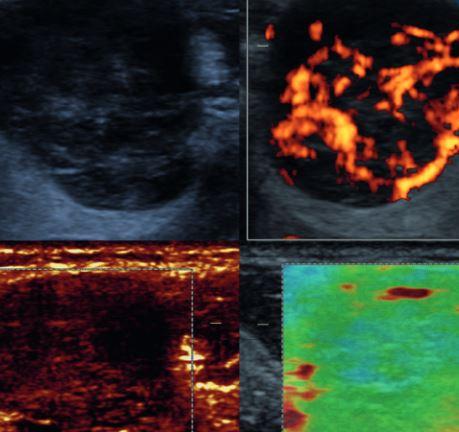

A- und B-Mode-Sonographie Kopf-Hals - DEGUM-Aufbaukurs

Do., 11.07.2024 - 12:00

Uhr